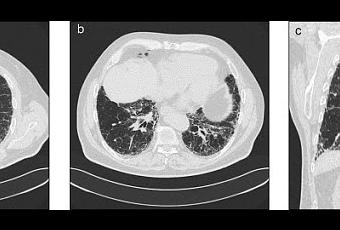

Tomodensitométrie thoracique en coupes parenchymateuses millimétriques (a, au niveau de l'artère pulmonaire; b, au niveau des bases; c, reconstruction frontale): aspect de fibrose pulmonaire idiopathique avec opacités réticulaires, bronchectasies par traction, et distorsion architecturale. In La Presse Médicale Volume 37, Issue 11, November 2008, Pages 1581 - 1590